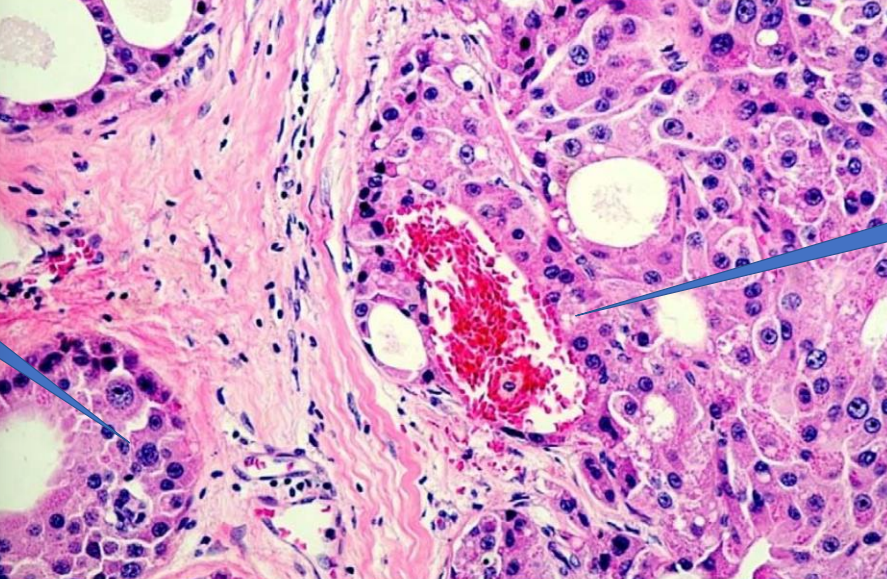

1- Blood vessel

2- Vascular invasion

1- Malignant Tumor

Malignant Tumor

Vascular invasion